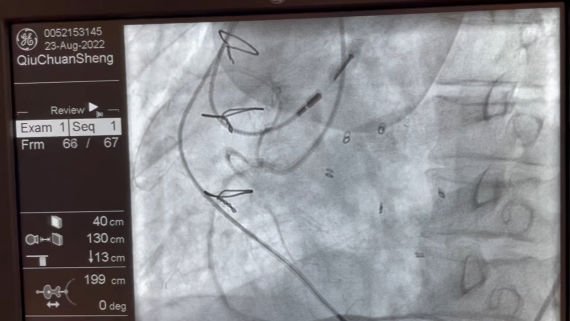

2.此次病例双生物瓣的瓣环均透视下不显影,即便造影模式也分辨不清楚瓣环,只能依靠三维超声引导下完成,术前的CTA扫描细节和结构特点预备方案,以及外科团队的经验尤为重要。

术中影像

TEE-第一个TAVR后大量PVL

TEE-第二个TAVR后PVL明显减少